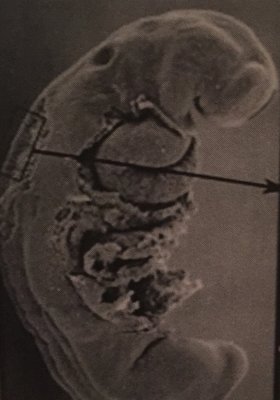

1)Ces 2 embryon appartiennent au même stade ? au stade 11 ?

Dans la fiche de carnegie de l'année dernière, cet embryon correspond au stade 12, peut être parce qu'on voit la placode otique ? Du coup je ne sais pas comment trancher ..

2) Cet embryon appartient au stade 13 ? Car on dirait qu'il y a un gonflement au niveau de la queue = membres inférieurs ou rien avoir et on est au stade 12 ?